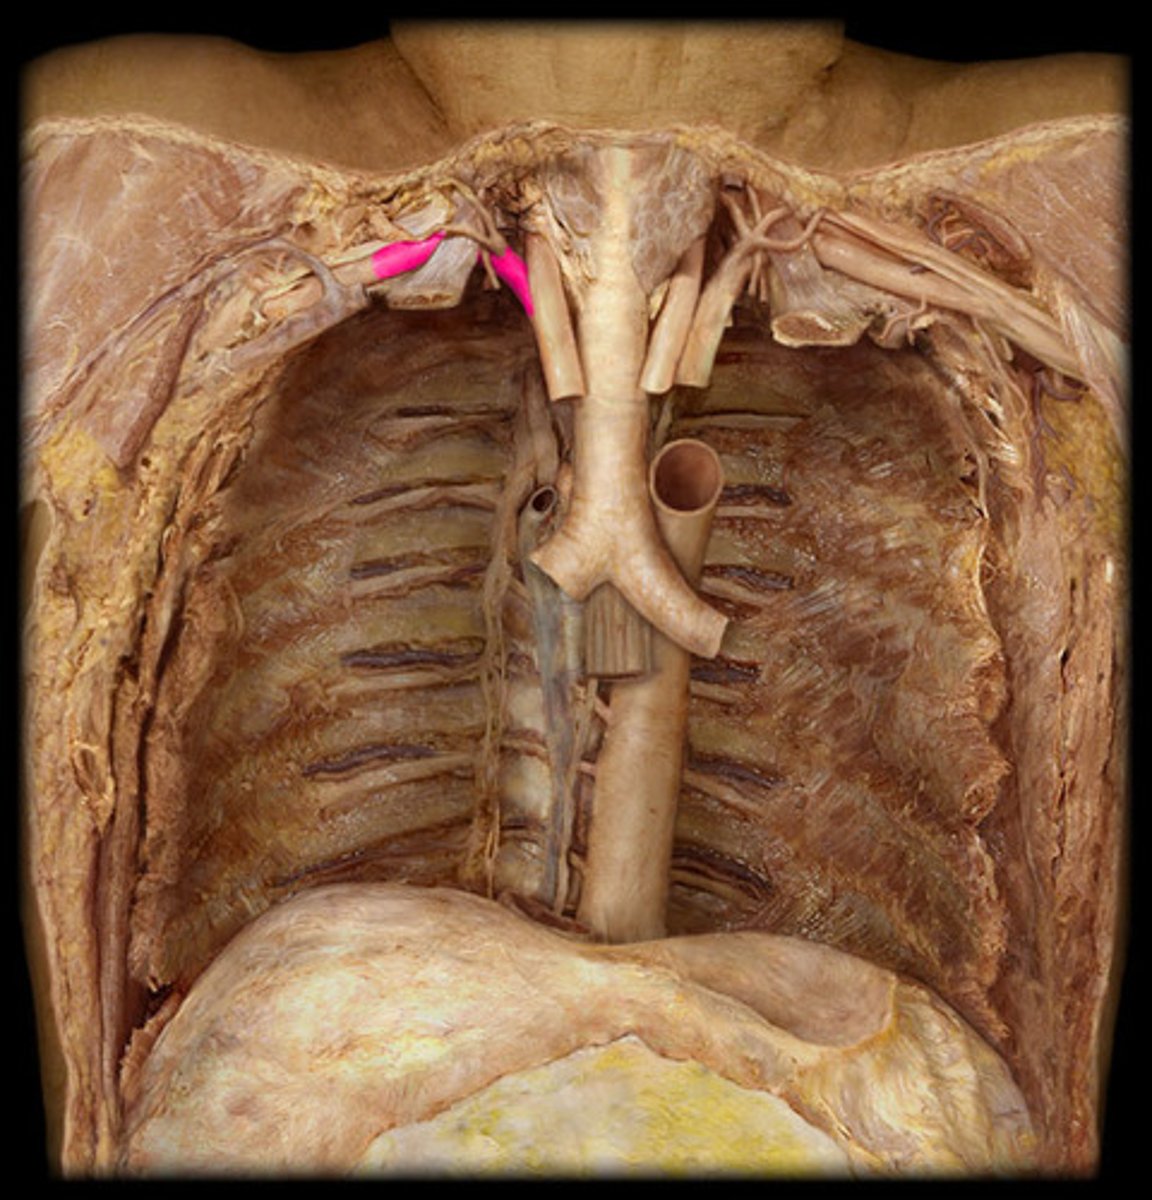

descending aorta

thoracic aorta and abdominal aorta

13

thoracic aorta

Portion, straight part on descending aorta, further down

*ta will run probe down pt. L side of heart

R. posterior intercostal artery

st

R ONLY

lower of the two white pins in ab aorta area